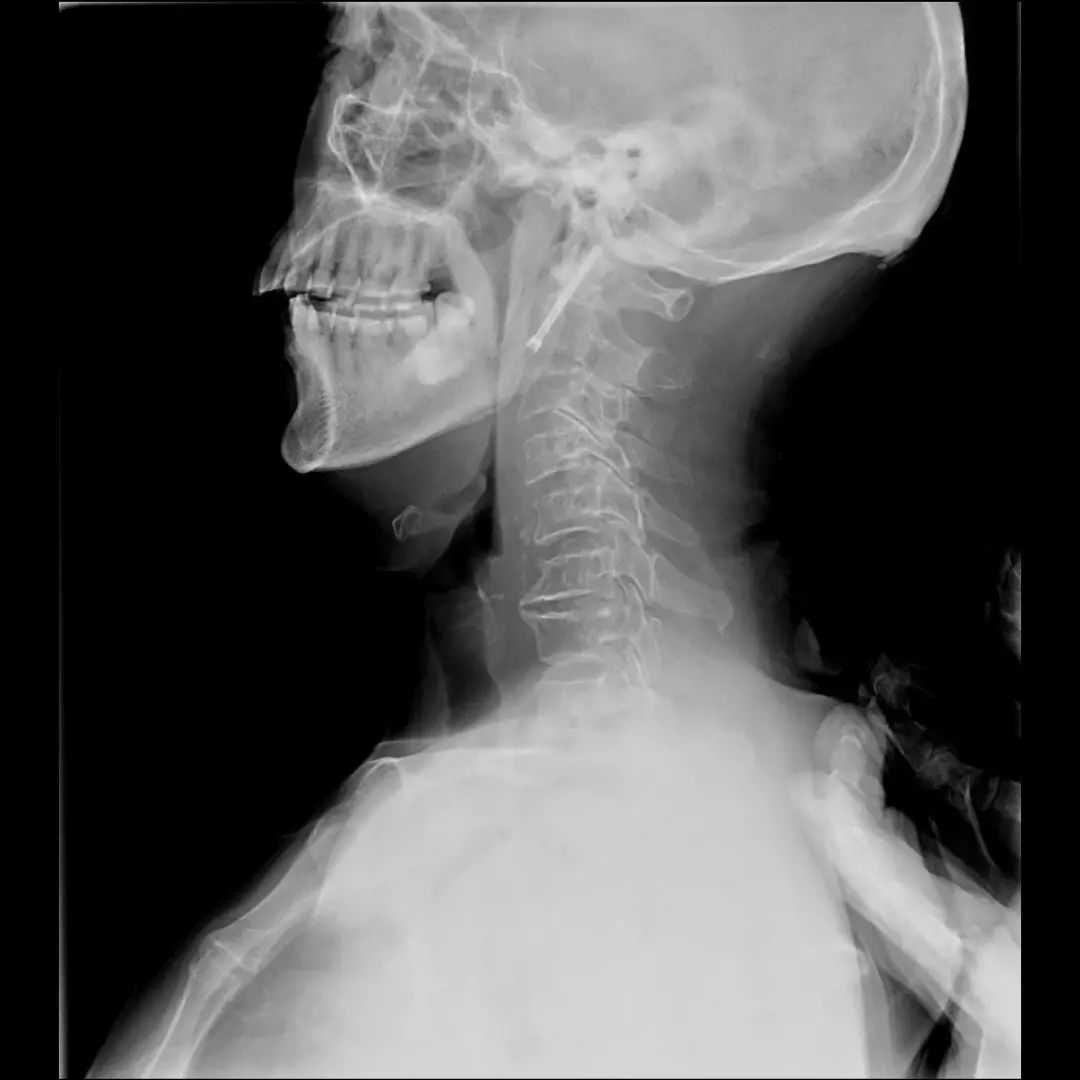

枕颈融合术